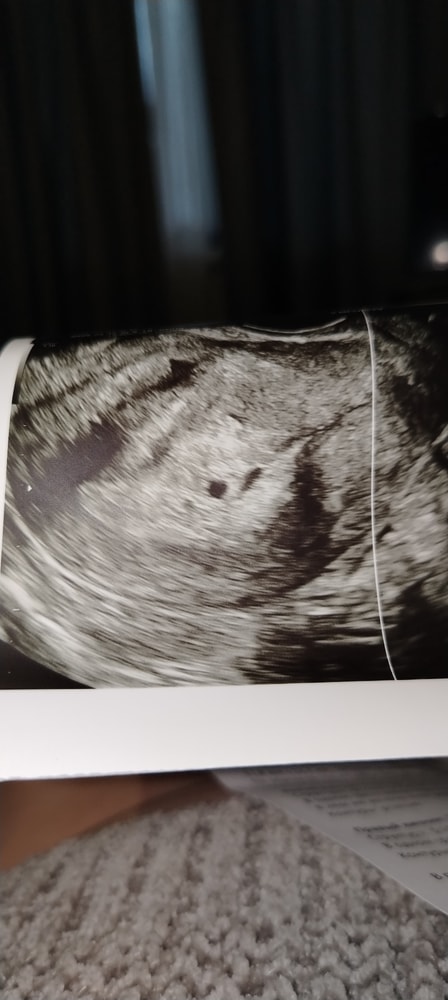

Узи было только вчера. Но вчера, конечно, меня врач напугал, сказал, что эбрион маловат для 6 нелель (3 мм, пя 15). А сегодня токсикоз исчез. На узи ведь нет смысла опять бежать? За день ничего не измени